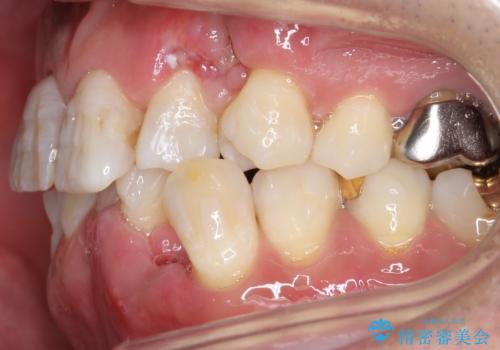

奥に引っ込んでいる歯をセラミックでかぶせたい 補綴前矯正 50代男性

- 神経が死んでいる前歯2本(右上21)をセラミッククラウンでかぶせたいとご希望され、来院された患者様です。

歯並びにより、そのままだときれいに被せ物をいれられない状態でした。

重度の叢生(歯並びのがたがた)のため、

患者様の「できるだけ短期間で治療を終わらせたい、セラミックが入れられたら良いので大がかりなことはしたくない」とのご要望により、3Dシミュレーションを何度も行い患者様とのコンサルを重ね、上顎左右犬歯と左下2を抜歯して②のプランである補綴前矯正(インビザライン)を行うことにしました。

小臼歯の歯根長が長いことを治療前にレントゲンで確認し抜歯部位を決定しました。